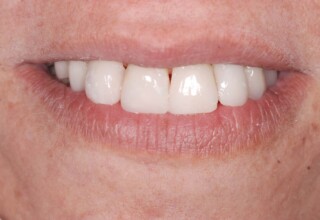

Οι όψεις πορσελάνης είναι ο καλύτερος τρόπος αντιμετώπισης αισθητικών προβλημάτων στην πρόσθια περιοχή του στόματος. Συνδυάζουν συντηρητική αφαίρεση οδοντικής ουσίας και πολύ υψηλή αισθητική απόδοση. Στο παρακάτω εκτεταμένο περιστατικό υπήρχαν: παλαιά σφραγίσματα, δυσχρωμίες, κακό σχήμα και μήκος δοντιών, κακή αναλογία δοντιών-ούλων. Έγινε προσεκτικός εργαστηριακός σχεδιασμός σε εκμαγεία απ’όπου προέκυψαν προσωρινές όψεις που τοποθετήθηκαν στο στόμα για δοκιμή και διορθώσεις. Όταν οριστικοποιήθηκαν οι μετατροπές, οι προσωρινές χρησιμοποιήθηκαν σαν οδηγός για τις μόνιμες. Οι πέντε μόνιμες όψεις πορσελάνης που κατασκευάστηκαν για τα πέντε πρόσθια δόντια της άνω απεκατέστησαν σχεδόν άψογα την αισθητική εμφάνιση της ασθενούς.

Αρχική εμφάνιση

Τελική εμφάνιση